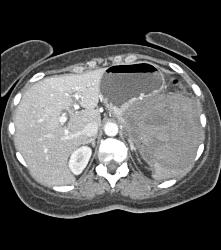

GIST Tumor